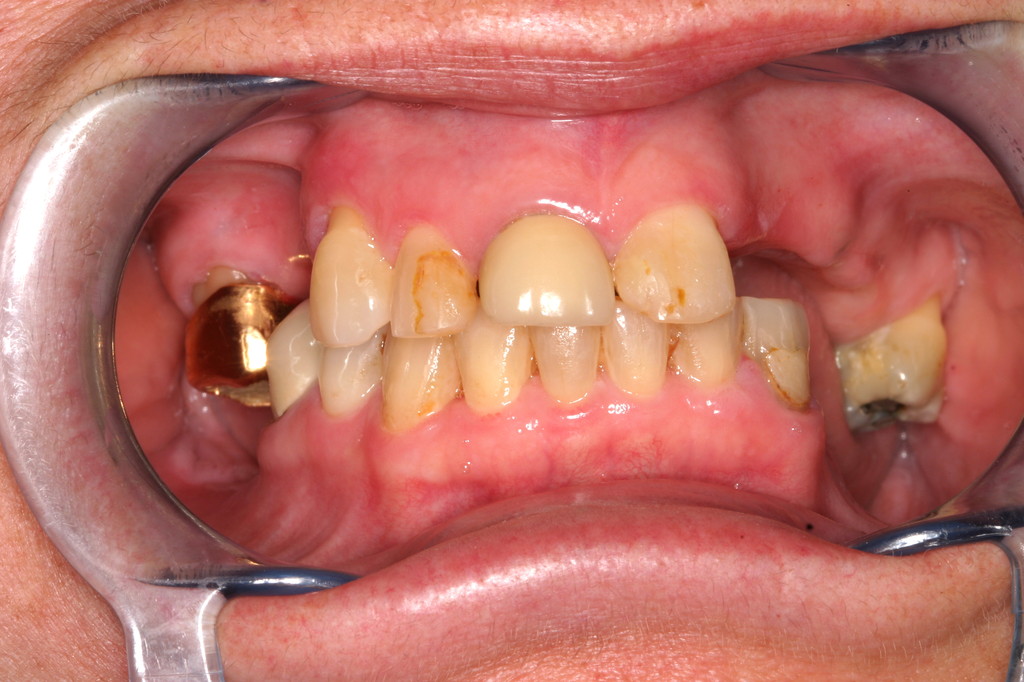

REHABILITACIÓN CON IMPLANTES Y CIRUGÍA PLASTICA PERIODONTAL.

REHABILITACIÓN CON IMPLANTES ,ENFERMEDAD PERIODONTAL AVANZADA.

REHABILITACIÓN ESTÉTICA CON IMPLANTES.